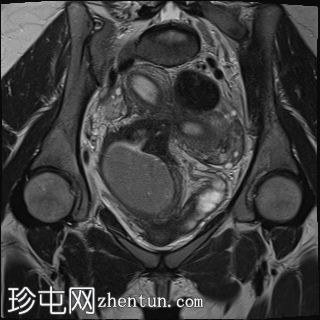

盆腔增强 MRI 检查增强了我们对 CT 扫描中发现的病变的理解。右肾发育不全,左肾肥大伴肾积水,双子宫完整,阴道隔膜,发育不全侧阴道积血。

双侧卵巢均有多个功能性囊肿,右侧卵巢可见黄体囊肿。

道格拉斯囊内可见少量游离液体。

左侧

泌尿

系统置入JJ支架,左侧输尿管下1/3扩张。